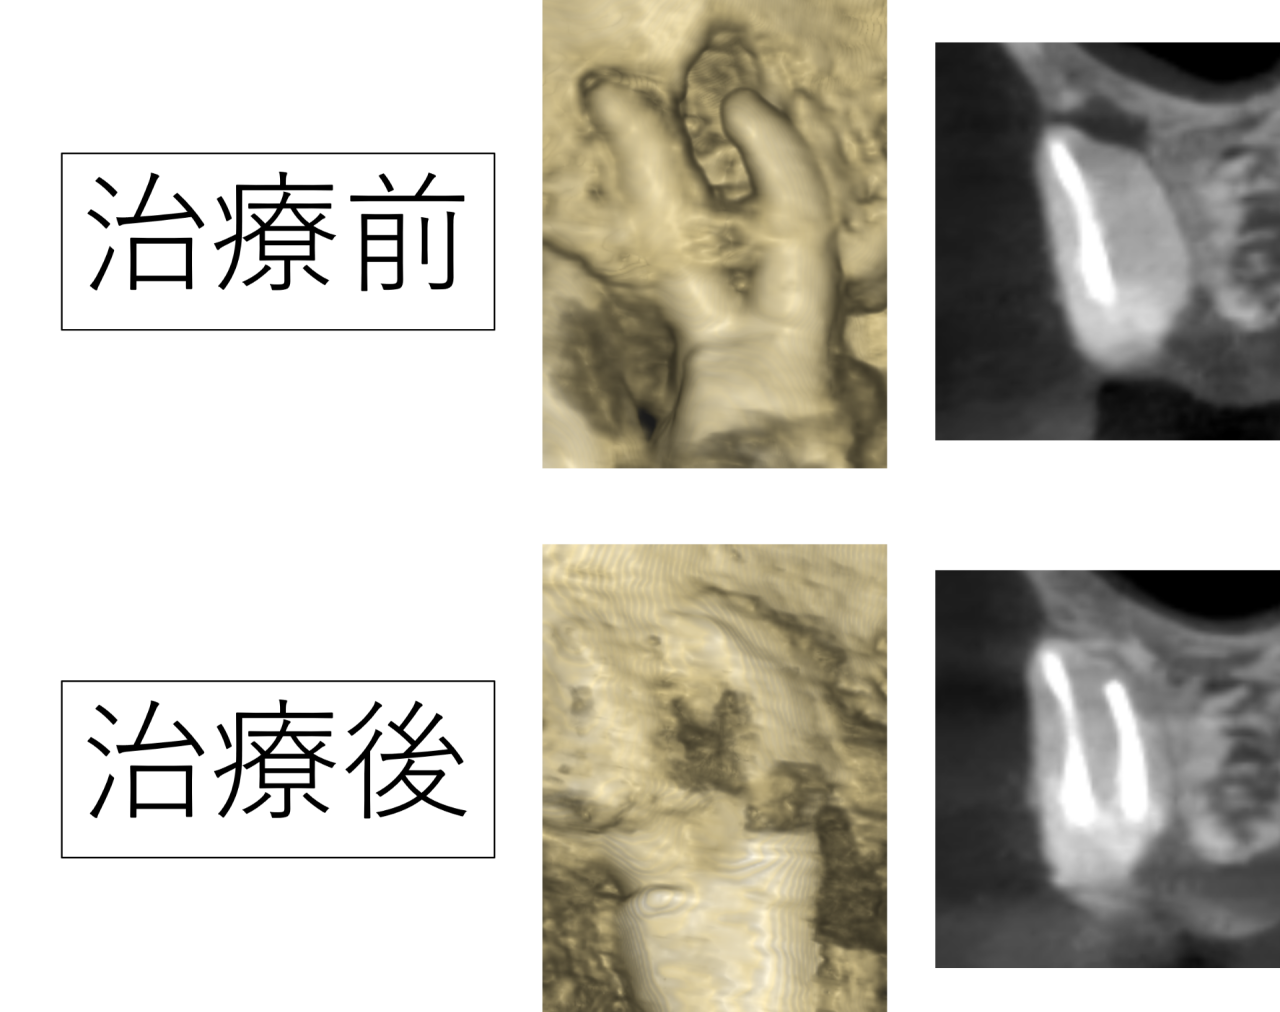

今回の右上の奥歯ですが、CTを撮影すると根っこに病気ができており、顎の骨が大きく貫通している状態でした。治療を受けて1年たっているとのことでしたが、この状態を見る限り、治療に不備があることが予想されました。

今回の症例では、詳しく確認した結果、根の中に神経(汚染組織)が取り残されていると予想されました。この取り残しが感染・炎症の元となり、治療後も痛みが続いていたと考えられます。

根の解剖学の話になりますが、神経は歯の根の真ん中にあるのが基本です。根の真ん中にない場合、一つの根に複数の神経があると予想されます。

病気がある根は真ん中に神経があるわけでなく、端に寄っていたため神経の取り残しが疑われました。

CTで得られた情報を元に、顕微鏡(マイクロスコープ)を見ながら慎重に器具で探していくと、予想通り取り残された神経が見つかりました。取り残された神経が感染し腐敗して炎症を起こし、痛みや骨が溶ける原因となっていたのです。

痛みはなくなり、骨が再生した

治療後かぶせ物を行い4年経過していますが、痛みもなく非常に良好です。

溶けていた顎の骨も再生し、空いていた穴が埋まりました。